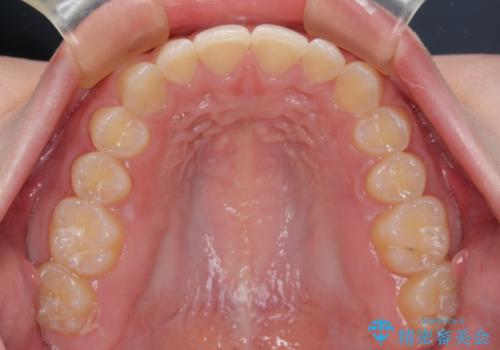

左上の歯列は補助装置により速やかに移動し、1年程度で奥歯の咬み合わせが改善され、1年3ヶ月の短期間でしっかりと仕上げることができました。